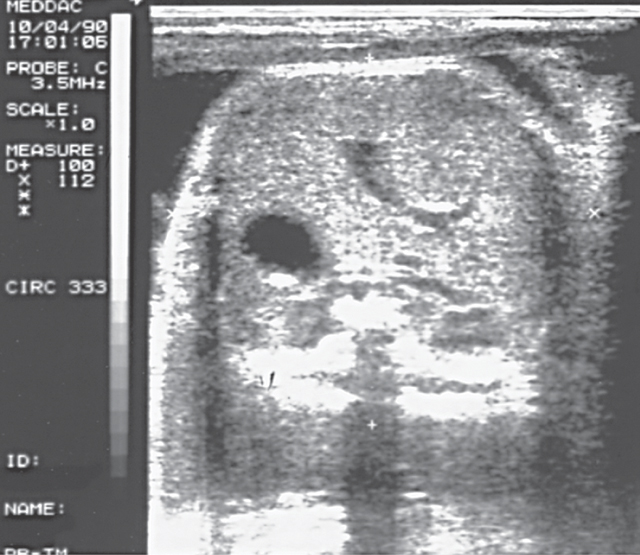

Figura 5. Ecografía de corte transversal abdominal.

• Para estimar la edad gestacional, el CA es útil solo cuando ninguna condición materna o fetal clínicamente aparente modificaría el crecimiento hepático. El AC es más útil para establecer la edad gestacional en la mitad de la gestación y los embarazos tardíos ( véanse las Figuras 4 5).

Figura 4. Circunferencia abdominal. Esta sección transversal del tercer trimestre del abdomen fetal muestra la unión de la vena umbilical y la vena porta izquierda. El estómago se ve en el lado izquierdo del feto. Ao, Aorta; Pv, vena porta; S, estómago; Sp, columna vertebral; U, vena umbilical; VC, vena cava.